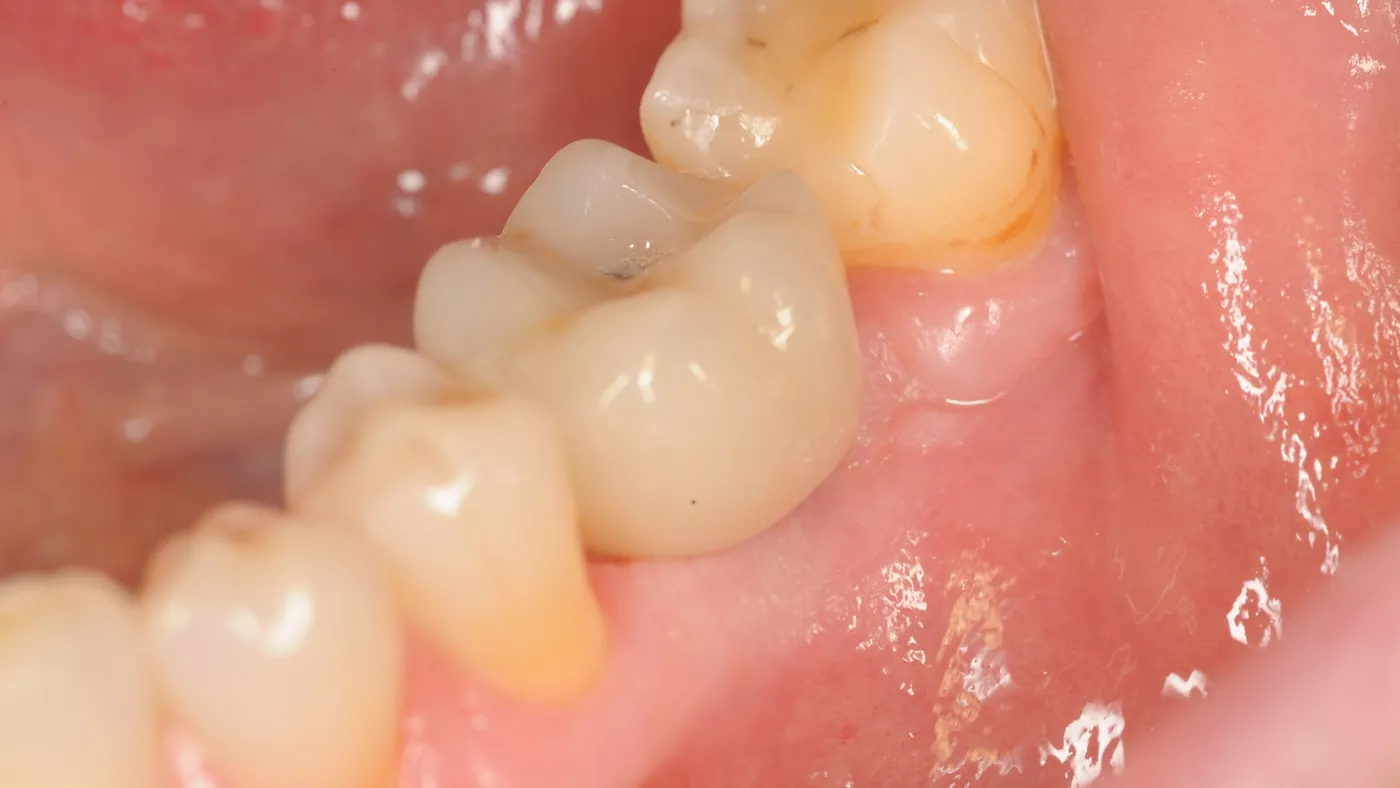

Under local anesthesia, a flapless implant surgery technique was performed at position #36. Due to the quality of the bone, staged drilling with continuous saline irrigation was performed in order to obtain a proper, safe insertion torque (Figs. 2-7). One implant (Straumann® BLT, Regular Neck, Roxolid®, Ø 4.8x10mm) was placed, and a torque of 42 Ncm was applied (Figs. 8-11).

The ISQ level was determined with the Osstell unit. After connecting the Type 54 Smartpeg, a score of 82 was obtained (Fig. 12). The decision to employ an immediate loading protocol has to take account of the surgeon’s personal experience and skills, insertion torque, ISQ levels and medical and dental characteristics of the patient. In this case, all these parameters were evaluated as excellent, and the immediate loading protocol was selected.